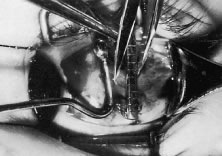

The globe then is gently elevated from the orbit or proptosed at the same time it is abducted or adducted to prepare for the incision. Elevation of the globe helps to separate the horizontal rectus muscle from the inferior rectus muscle so that the inferior rectus muscle is not cut when the incisions are made. The conjunctiva is grasped by the assistant with a Manhattan toothed forceps (Fig. 10). This forceps has teeth that are angled outward and are designed to grasp conjunctiva, as well as the deeper subconjunctival tissue, so that when the blunt-tipped Westcott scissors cuts into the tented tissue, an incision is made into the conjunctiva and Tenon's capsule (Fig. 11A and B). If the incision does not completely penetrate Tenon's capsule and the intermuscular septum to the scleral surface of the eye, additional tissue (anterior Tenon's tissue and/or intermuscular septum) is grasped with the Manhattan forceps and at least one additional cut is made.

A Stevens' tenotomy hook is passed by the surgeon into the incision and is rotated so that it can be slid underneath the muscle insertion with the tip of the hook held tangential to the globe (Fig. 12). The hook should be passed 2 to 3 mm posterior to the expected location of the muscle insertion. Care is taken not to incorporate intramuscular septum or other adventitial tissue on the hook. When the lateral rectus muscle is secured with the Stevens' or Jameson muscle hook, care should be taken not to bring the inferior oblique muscle up to the insertion (Fig. 13). When the muscle is secured with the Stevens' hook, the hook and the inferior edge of the muscle insertion are elevated and a Jameson muscle hook is passed between the tented muscle tissue and the sclera to secure the muscle at its insertion (Fig. 14). Care is taken to include the entire insertion of the tendon on the hook. The tip of the Jameson hook is gently elevated by depressing the heel of the hook. This maneuver helps to ensure that the entire tendon of the muscle remains captured on the hook. A Stevens' tenotomy hook is placed in the incision, this time anterior to the insertion beneath the conjunctiva (Fig. 15). The Stevens' hook is passed posterior over the orbital surface of the muscle (Fig. 16). Gentle pressure on the Stevens' hook is directed posterior so that the check ligaments and Tenon's tissue that overlie the muscle belly are separated from the muscle capsule with blunt dissection. The hook usually is passed posterior for about 10 mm. When recessing a lateral rectus, attachments between the underside of the lateral rectus and inferior oblique are broken (Fig. 17). Two or three passes over the muscle are made, and, with simultaneous countertraction on the Stevens' hook and the Jameson hook, the conjunctiva is elevated and pulled over the tip of the Jameson hook (Fig. 18A and B).